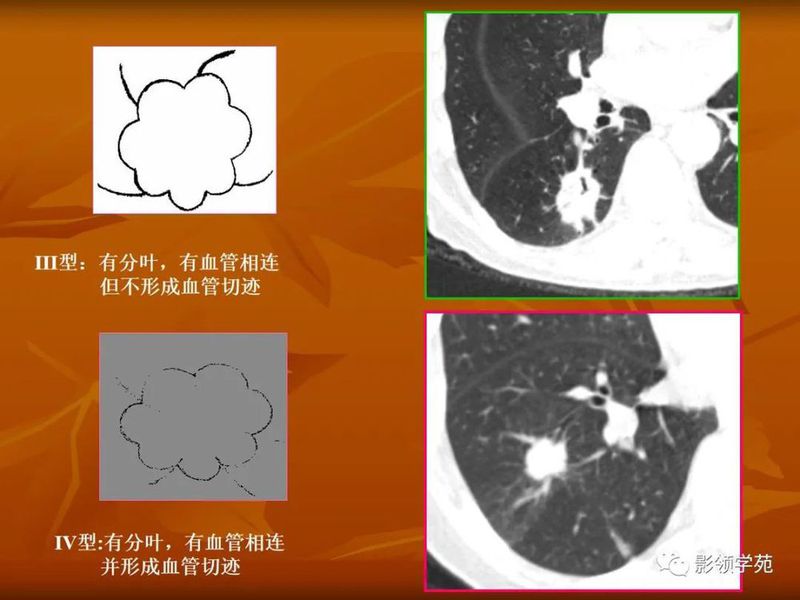

(1)较大含空洞性肿块,洞壁较厚,大于15mm,空洞外壁有分叶、毛刺,洞壁凹凸不平有壁结节,增强可见不规则强化,周围未见明显卫星病灶时,首先考虑周围型肺癌;癌性空洞洞壁一般肺门侧较厚,空洞多偏于外侧,伴有同侧淋巴结肿大更支持肺癌诊断。